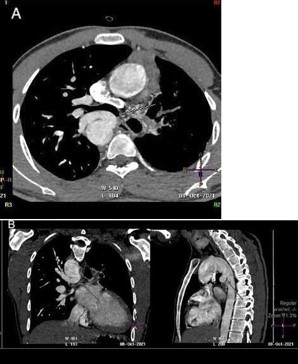

CT angiogram of chest shows complex cardiac disease including right-sided aortic arch (Figure 1), ventricular septal defect and overriding aorta (Figure 2). Non-visualization of the pulmonary trunk (Figure 3).

Figure 2: Contrast-enhanced reconstructed 3 chambers view of the heart showing a ventricular septal defect and overriding aorta.